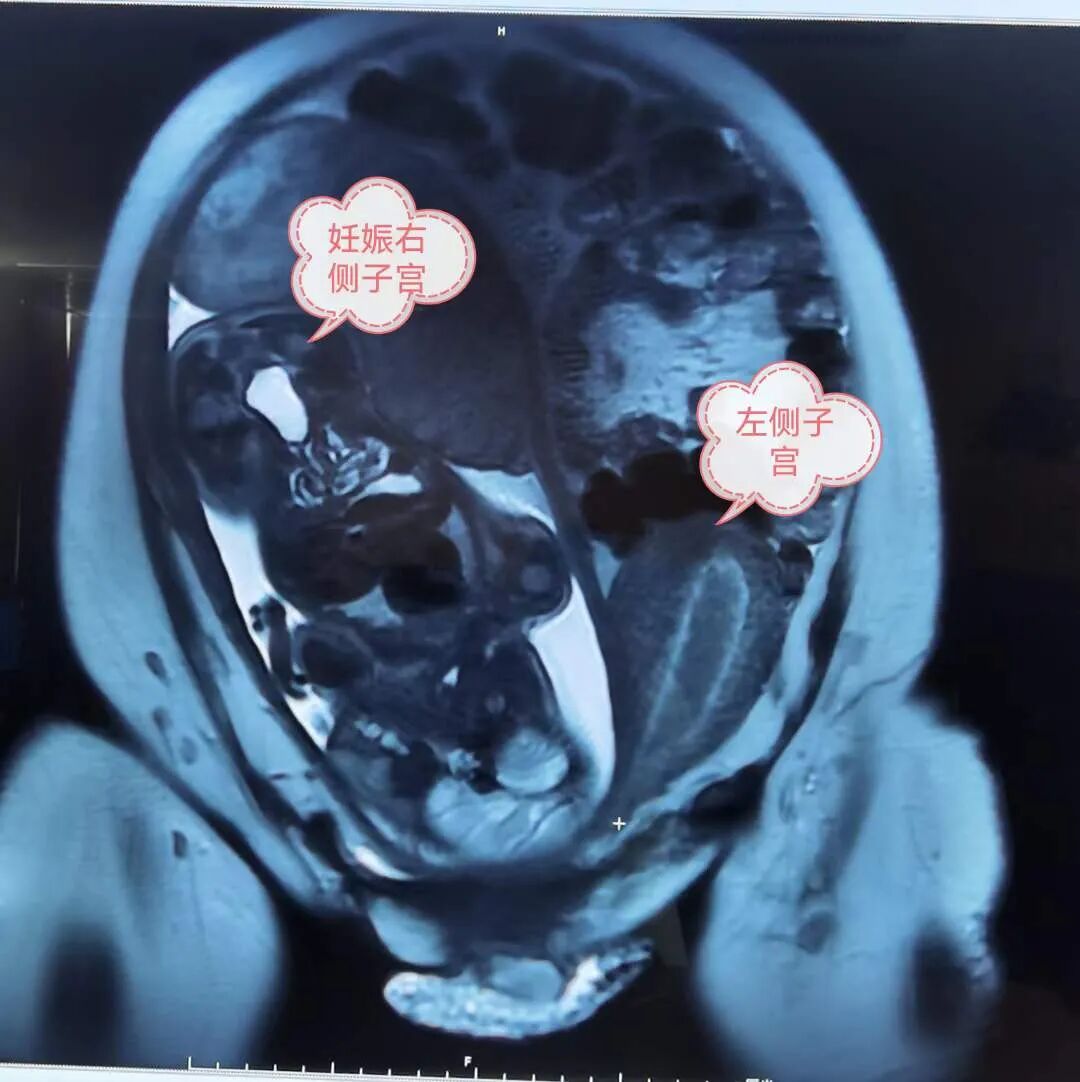

合并双子宫、双宫颈、双阴道

近日,东莞市厚街医院产科收治了一名罕见疾病的孕妇:患有先天性膀胱外翻合并双子宫、双宫颈、双阴道、骨盆和盆底发育异常,因诊断为“34+3周妊娠,左侧会阴肿物脱出4天”而要求入院待产。

据了解,膀胱外翻发病率为百万分之一,而在女性中发病率更低,该孕妇为膀胱外翻术后患者,再加上其有双子宫、双宫颈、双阴道等生理结构的特殊性,实属罕见。

“我从医几十年,还是第一次遇到这样的病例,确实罕见。”我院妇产科主任、主任医师郑穗瑾表示,“由于孕妇的特殊生理构造,如不及时娩出胎儿,可能因早产临产,先露下降导致产道及周围组织严重裂伤”,“经评估,左侧子宫脱垂,右侧妊娠子宫宫颈管己消退,宫口宫一指,随时可能临产,且该孕周胎儿分娩后存活几率较大,我们才会进行剖宫产手术。”